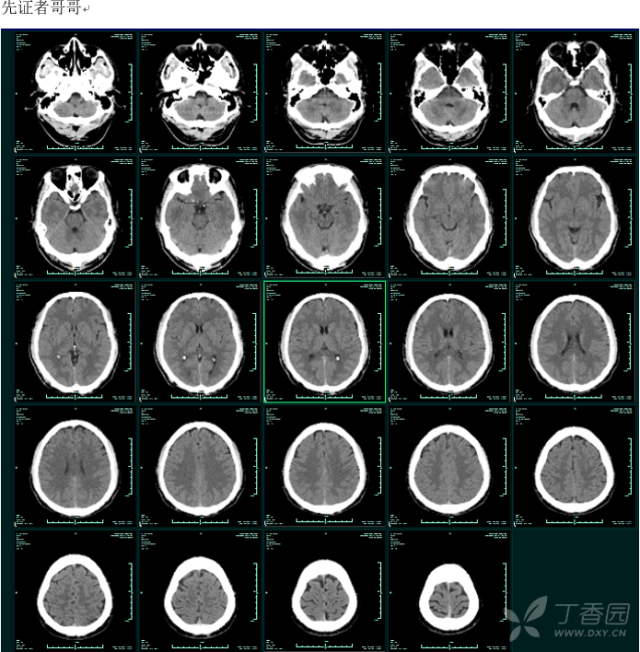

典型头颅CT对称性钙化表现--可疑1家系家族性